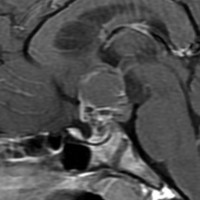

ちょっと大きな頭蓋咽頭腫です

嚢胞(液体が入っている袋)の部分と,腫瘍細胞が固まっている実質部分が入り交じっています。このくらいの大きさになってしまうと,下垂体機能を残すことはとても難しくなります。視神経が圧迫されて視力低下と視野障害を生じます。第3脳室が腫瘍で閉塞していて水頭症になっていますから知能の活動が低下します。

腫瘍を摘出するのに危ないのは,脳の血管の損傷です。左では白く,右では黒く線状に移っているのが太い脳動脈です。これら以外にもたくさんの細い重要な動脈が絡んでいます。

幸いこの患者さんの腫瘍は摘出できて患者さんは元気になりました。でもこのくらいのサイズになると手術がいつもうまくいくとは限りませんし重大な障害が残ることもあります。